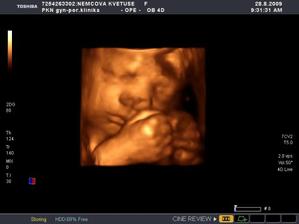

Nová naděje. Bohužel to bylo opět stejné, jako již dvakrát předtím. Třetí revize, třetí ztráta naděje. Jsem po laparoskopii a hysteroskopii a čekáme na výsledky imunologie v Plzni. Pak se uvidí co dál. V únoru 2009 nám v Sanusu doporučili ještě dva měsíce domácího snažení. Tak jsme se snažili a nyní napjatě sledujeme čárku. HCG nám krásně stoupá, 20. den po ovulaci je 2066. Máme 1. fotku dutinky. Přes nejrůznější potíže a patnáctidenní hospitalizaci nám miminko krásně roste. 22. dubna konečně po čtrnácti dnech ukázalo nosánek, máme nosní kůstku, NT je 2,0. Máme vše, co máme mít a rodiče se dnes poprvé společně dívali na ultrazvuk. Viděli mě i 4D, to koukali. Odnesli si video a teď na něj pořád koukají. Další kontrola náš čeká 5. května, opět ultrazvuk, triple testy a poradna. Trošku změna situace, mamka se mnou leží od 27. dubna v nemocnici, ale já ji dělám radost, rostu, 16.6. už vážím 360 gramů a od 5.6. ji kopu a ona o tom ví. Od 10. 6. se nám začal malinko měnit nález až jsme museli 10. 7., gr. h. 24+2 na cerclage, potom jsme měli zánět ledvin a astmatický záchvat. Pořád mamce tvrdlo břicho, tak se bez infuzí neobejde. 18. 7. se ještě objevilo krvácení, ale nebylo to nic závažného, byli jsme na ultrazvuku a vážím 908 gramů. V pátek 24.7. se to zlepšilo a kapeme na nejnižší rychlost, hurá. Mamka zatím nesmí chodit, má to slíbeno na 2. září. Kapeme sice na nejvyšší rychlosti, ale na ultrazvuku 4.8. mám odhad 1280 gramů. Dne 18.8. jsme byli na ultrazvuku a mám odhad 1750 gramů, mám trochu víc plodové vody a tak si tam plavu jako v bazénku. Dne 28.8. jsme byli s mamkou zase na ultrazvuku, vážím už 1950 gramů, mám udělaný krásný 3D fotečky, vody už nemám tolik moc, tak je mamka ráda. Jen se nám zase zkrátil čípek, už mě tam drží jen steh a 13 mm, ale držím mamce pěstičky, aby jsme vydrželi. No a taky si musím zvykat, mamka totiž má už dovoleno chodit na wc, a já jsem byl zvyklej, že pořád leží. Je sice z toho unavená, ale šťastná. Já jsem jí ještě udělal radost, že jsem se přetočil hlavičkou dolů. Dne 1.9. se mi konečně podařilo zbavit se té nitě, co tam mamka měla. Všichni jsou překvapení, jak se to mohlo stát, ale steh je pryč. Dne 10. 9. jsme s mamkou byli zase na ultrazvuku, vážím 2368 gramů (33+1). Hrdlo máme sice jen 9 mm, ale já se tam ještě udržím! Plodové vody mám už akorát, mamce klesly jaterní testy, žlučové kyseliny jsou v normě, tak má radost. Tak dnes 17. 9. jsem se byl zase vážit, mám 2517 gramů. Hrdlo má mamka jen 6,7 mm s obrovitým funnelingem, ale pořád drží. Denně mi točí monitory, mám je vzorné a pořád nemůžu přijít na to, jak ty sondy odkopnout. 26.9. pustil pan doktor mamku na propustku, byla poprvé 12 hodin mimo nemocnici, byli jsme na zahradě, grilovali jsme a já jsem babičce, dědečkovi a strejdovi předváděl, jak umím krásně kopat. Mamka byla moc šťastná. Večer se vrátila do nemocnice, dala si po 23. hodině sprchu a když usínala, tak jsem ji hodně překvapil, vypustil jsem svůj bazén. A tak se nešlo spinkat, ale na porodní sál. Šlo to pěkně a přesně ve 4.00 hodin jsem se narodil za skvělé asistence mého tatínka, který mamince na sále moc pomáhal. Vážím 2740 gramů a měřím 50 cm. Dosáhl jsem gestačního stáří 35+4. Rodiče a velká spousta lidí kolem ze mě mají velikánskou radost. Trošku jsem odmítal v inkubátoru dýchat, tak mě 1 den pomáhal CPAP. Večer mi ho vzali a teď už se snažím sám. mamka za mnou chodí a já jsem rád, když ji vídím. Dnes jsem na ni poprvé otevřel očička, snažím se papat, dnes už ze stříkačky. Tatínek je ze mě unešenej a já jsem rád, když mě přijde pohladit a vyfotit.